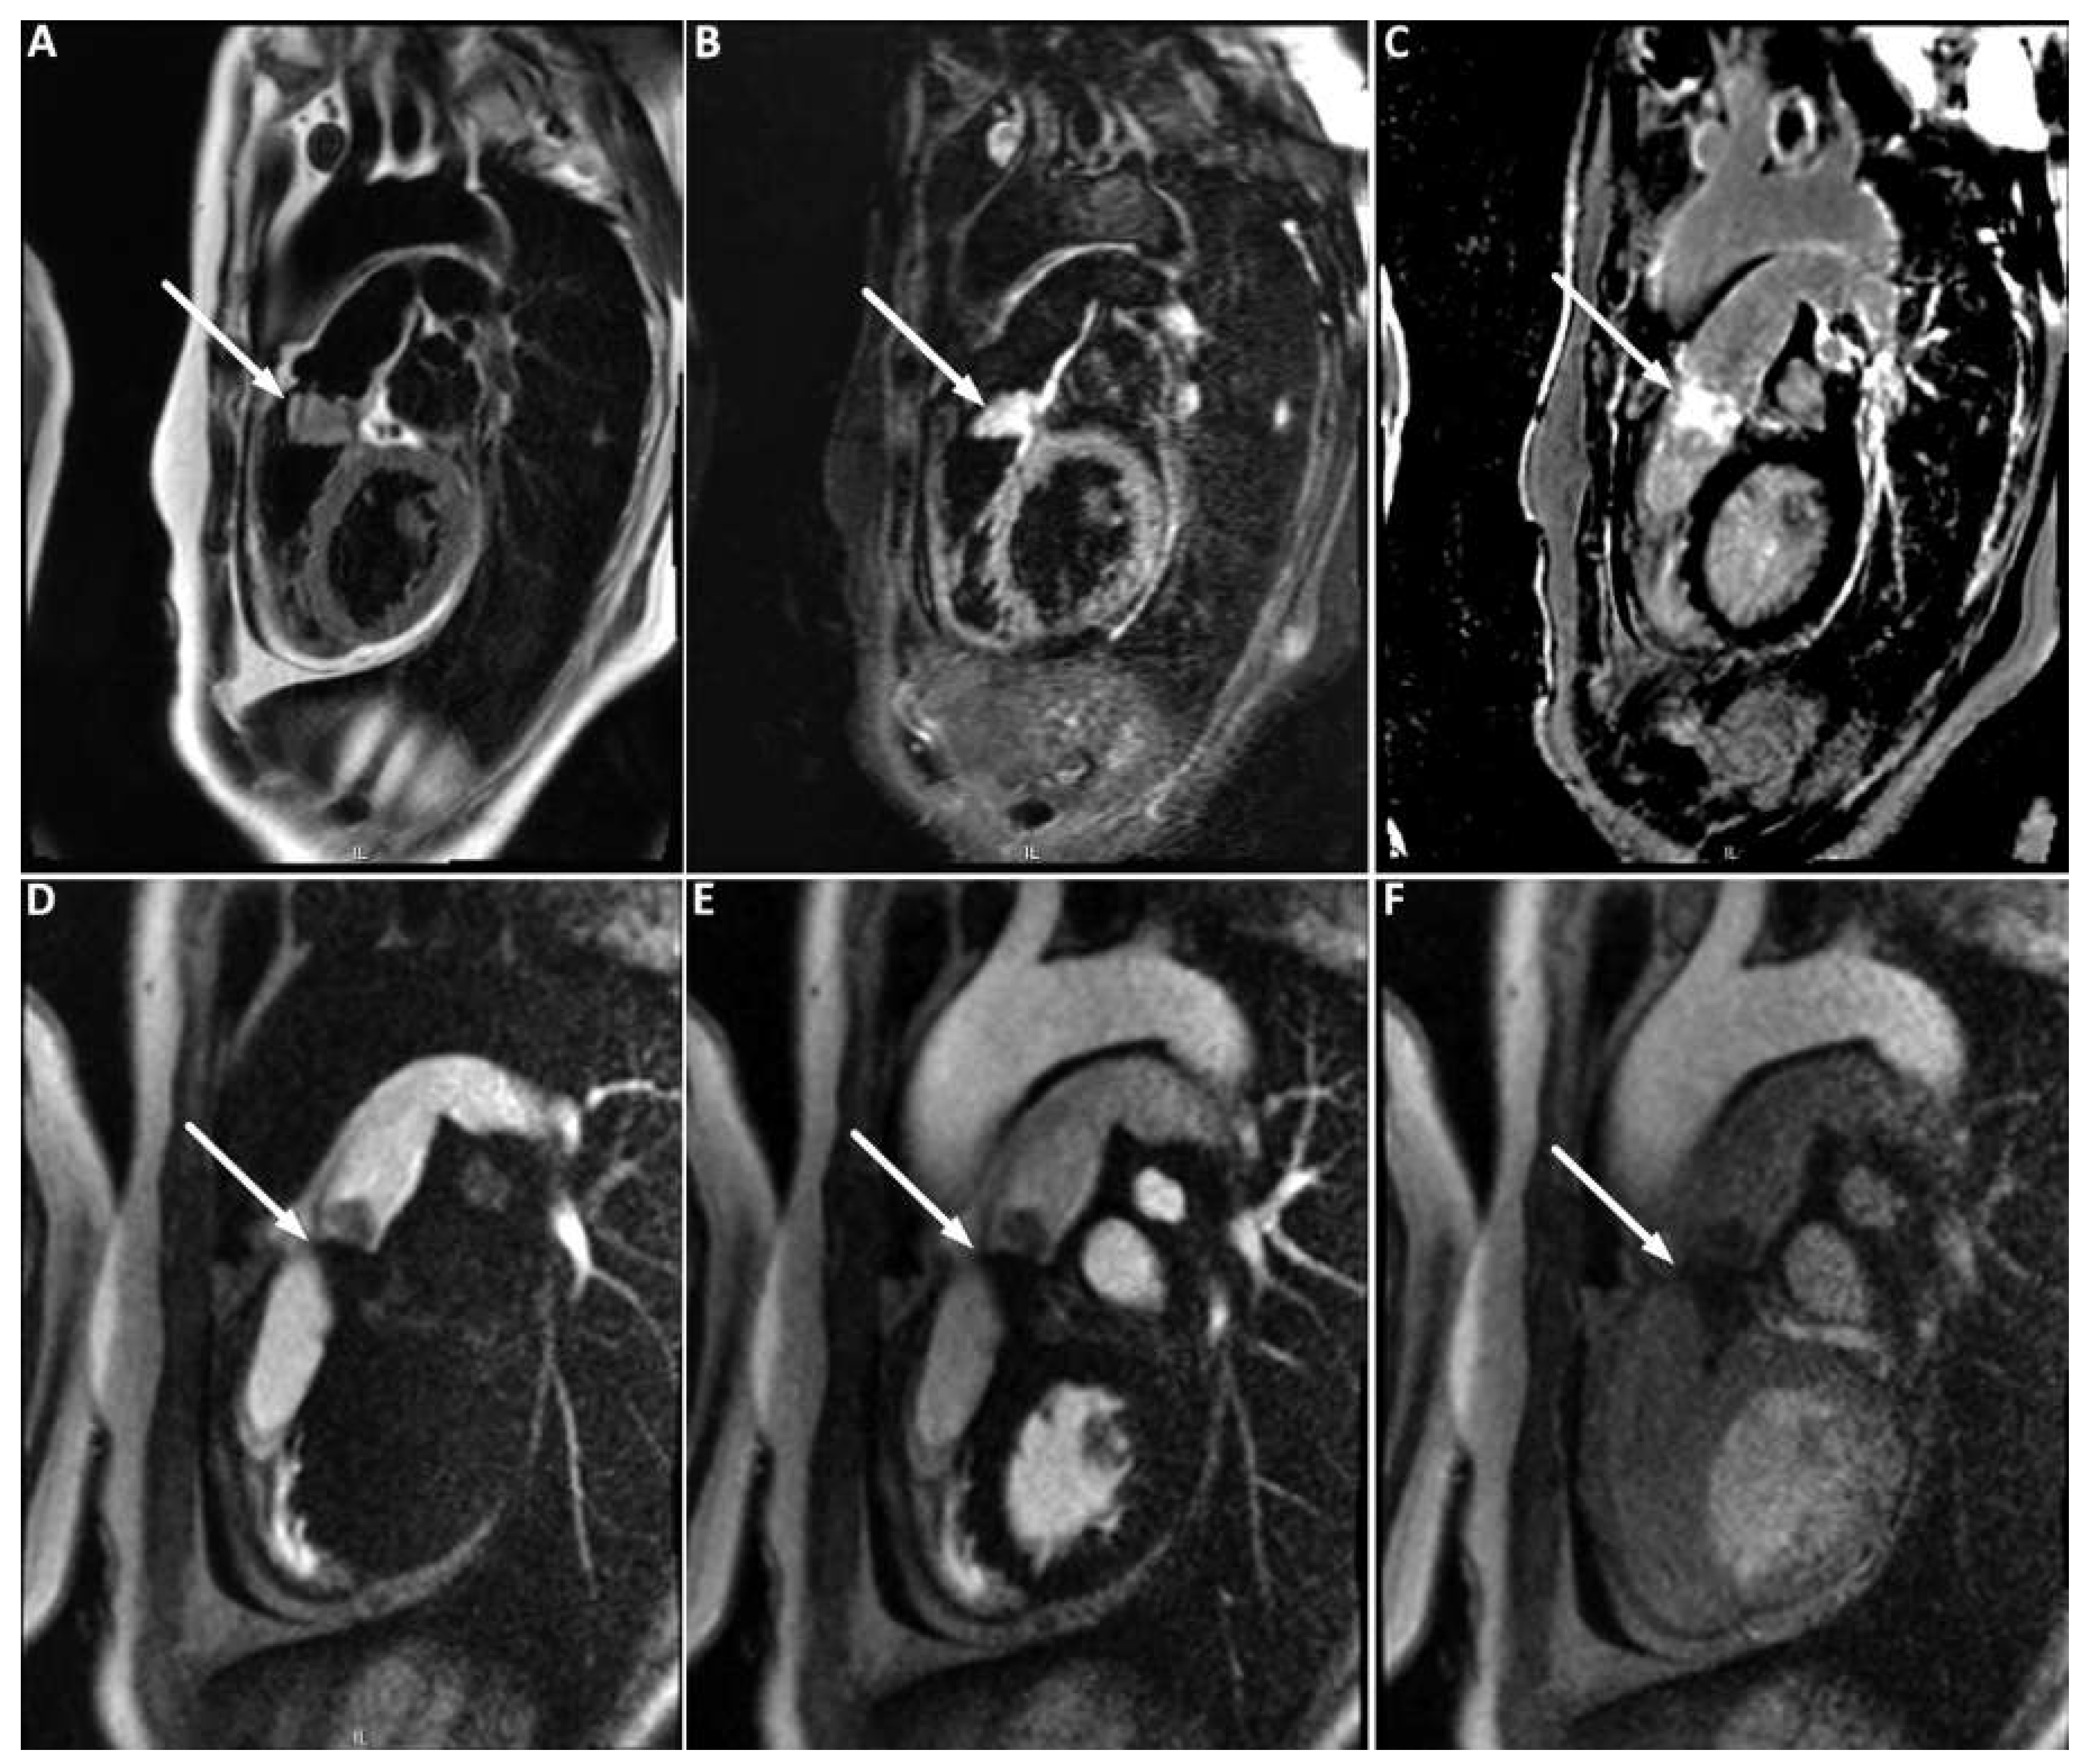

The patient was promptly referred to our institution where cardiac computed tomography (CT) revealed a 25 × 35 × 24 mm mass attached to the RVOT and extending into the pulmonary trunk through the pulmonary valve (Figure 2). After intravenous injection of 60–80 ml iodinated contrast material, late image acquisition showed inhomogeneous enhancement of the mass and mural enhancement of the pulmonary trunk suggestive of infiltration. This technique in the context of cardiac CT consists of acquiring images 60 seconds after CT angiography in order to optimise tissue enhancement. Fludeoxyglucose (18F) positron emission tomography-CT (18F-FDG PET-CT) revealed mild metabolic activity of the mass, with no signs of metastasis (Figure 3). Finally, cardiac magnetic resonance imaging (MRI) confirmed proximal extension of the valve mass, 4 cm towards the pulmonary trunk, without apparent invasion of the bifurcation (Figure 4). A hyperintense signal in T2-weighted images indicated oedema, whereas moderate signal-enhancement during resting perfusion suggested rich vascularisation. Intense signals on gadolinium enhancement sequences suggested rich extracellular content (fibrosis or extracellular matrix), but no significant necrosis (Figure 5).

Figure 5. (A) T1-weighted image; the mass (arrow) has a signal iso-intense to the myocardium. (B) T2-weighted image; the mass has a signal hyper-intense to the myocardium indicating presence of tissue oedema. (C) Late gadolinium enhancement sequence; the mass shows bright enhancement indicating rich vascularisation. (D to F) Perfusion imaging; (D) contrast in the right cardiac chambers; (E) contrast in the left cardiac chambers; (F) contrast enhancing the myocardium: the mass shows moderate first-pass enhancement with peak signal intensity lower than that of the myocardium.